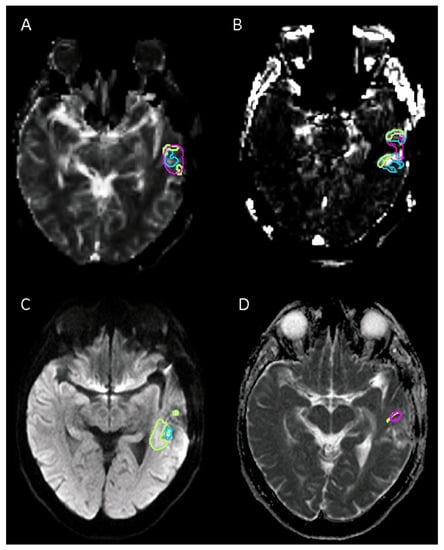

2.3.1. MRI Delineation

2.3.2. 18F-FET PET/CT Delineation

2.4. Calculation of Spatial Correlation and Overlap between Different Sequences of MRI-Based and 18F-FET PET-Based Tumor Volumes